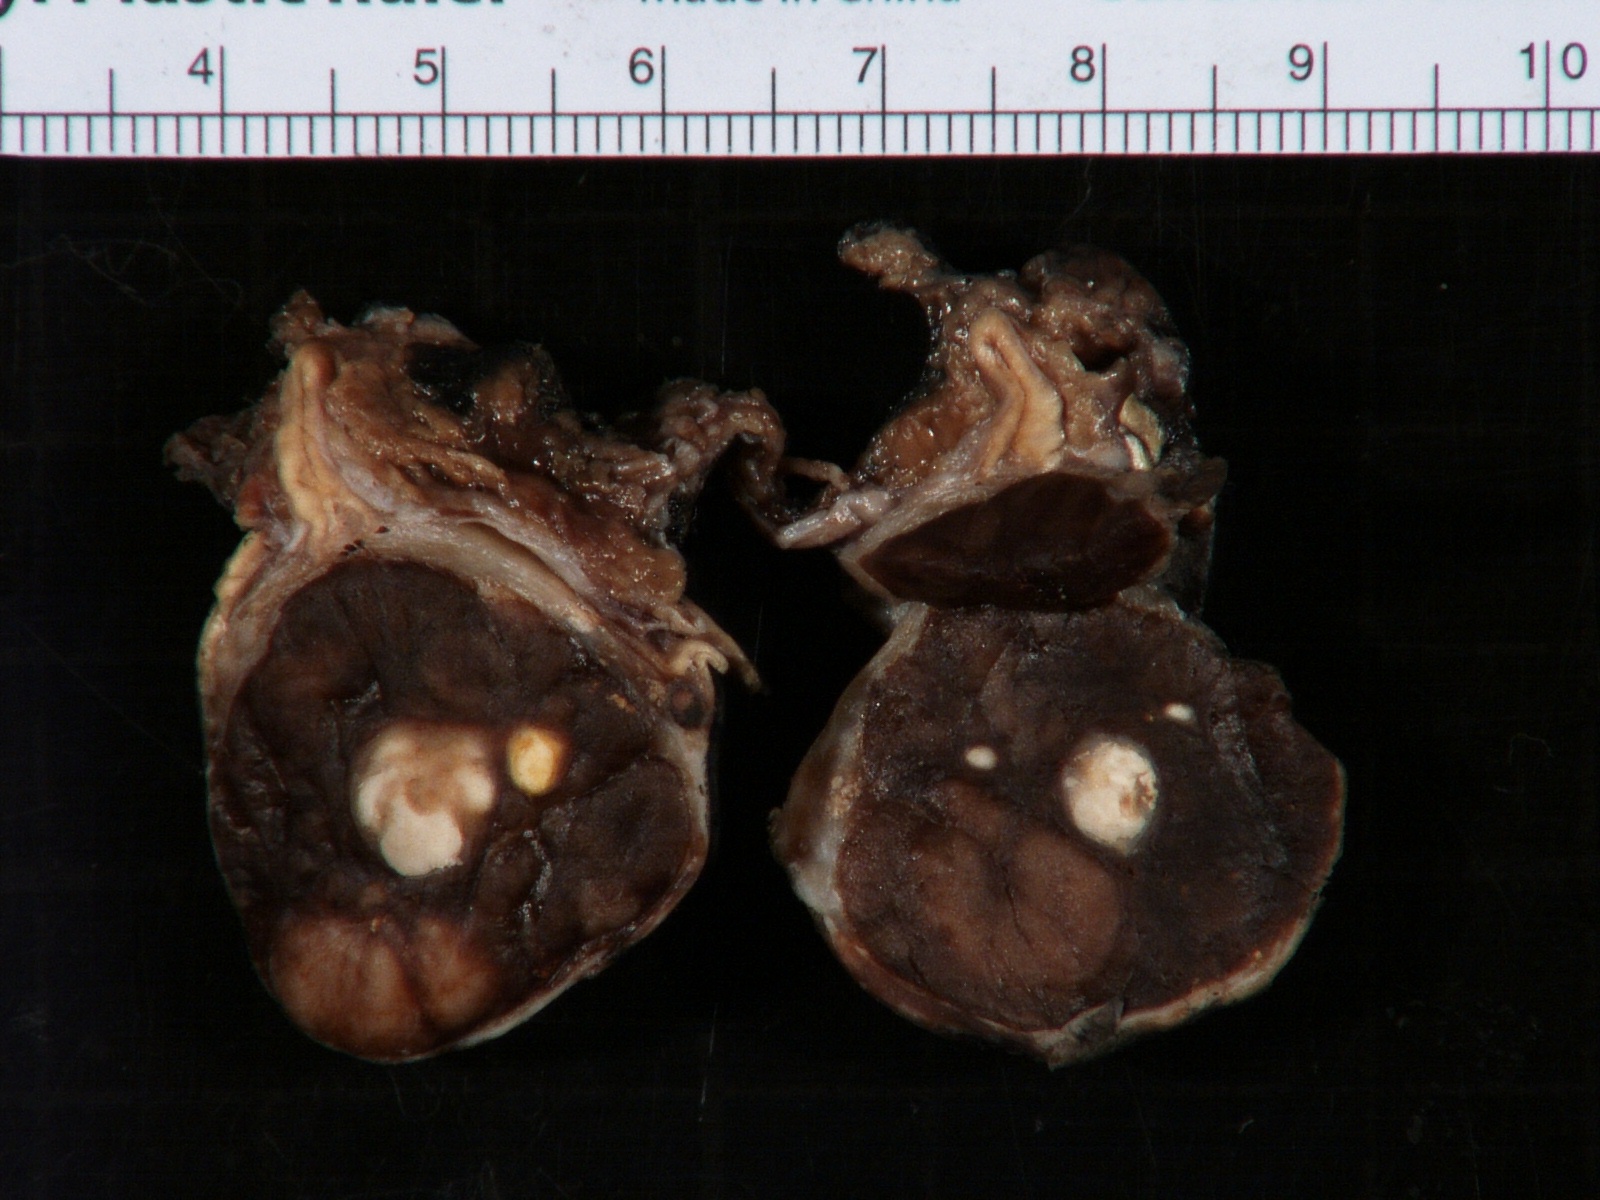

- More homogeneous and mature appearance than neuroblastoma

- Varies by subtype, from circumscribed ovoid mass to large multilobulated tumor

- Stroma rich, nodular subtype: area(s) of stroma poor, immature tumor are usually hemorrhagic with well defined borders (J Natl Cancer Inst 1984;73:405)

- Calcification (chalky white, yellow areas) and cystic degeneration may occur

- If large, adrenal gland may be difficult to identify